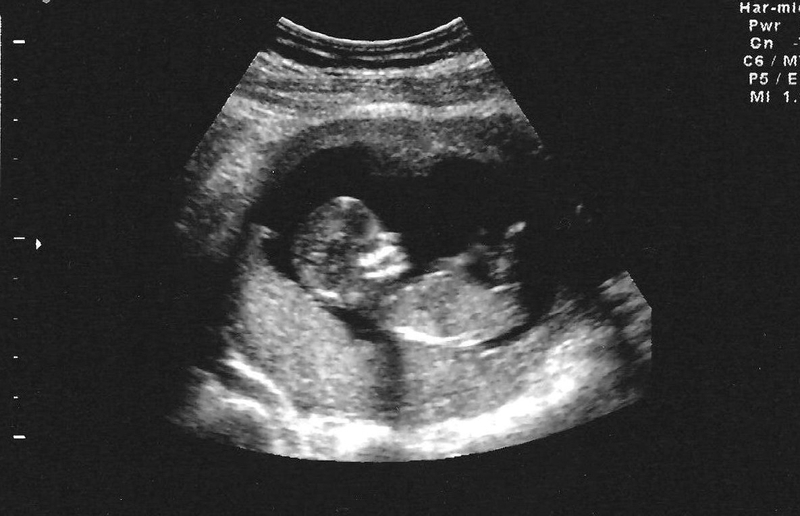

Hiện tượng tụ dịch màng nuôi có thể gây ra tình trạng chảy máu âm đạo, co thắt và kèm theo chuột rút. Tuy vậy, đôi khi thai phụ sẽ không có bất kỳ dấu hiệu nào, thậm chí là không đau bụng. Hiện tượng tụ máu ở dưới màng đệm mà chỉ phát hiện khi siêu âm.

Tụ dịch màng nuôi: Nguyên nhân và cách điều trị 1 Tụ dịch màng nuôi hay được gọi xuất huyết màng đệm là hiện tượng thường gặp ở phụ nữ có thai